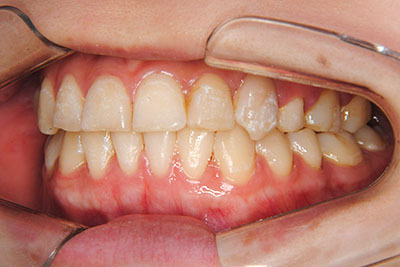

マルチブラケット装置(T21ブラケット)に加えて口の中のゴムをたいへん頑張って使っていただいた結果、治療前の予想期間1年から1年半であったところ、10カ月で動的治療を終了できました。上下真ん中のズレも治りぴったりになりました。 これからは歯並びの維持安定のためリテーナー(保定装置)を使いながら定期健診となります。